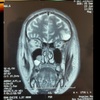

4